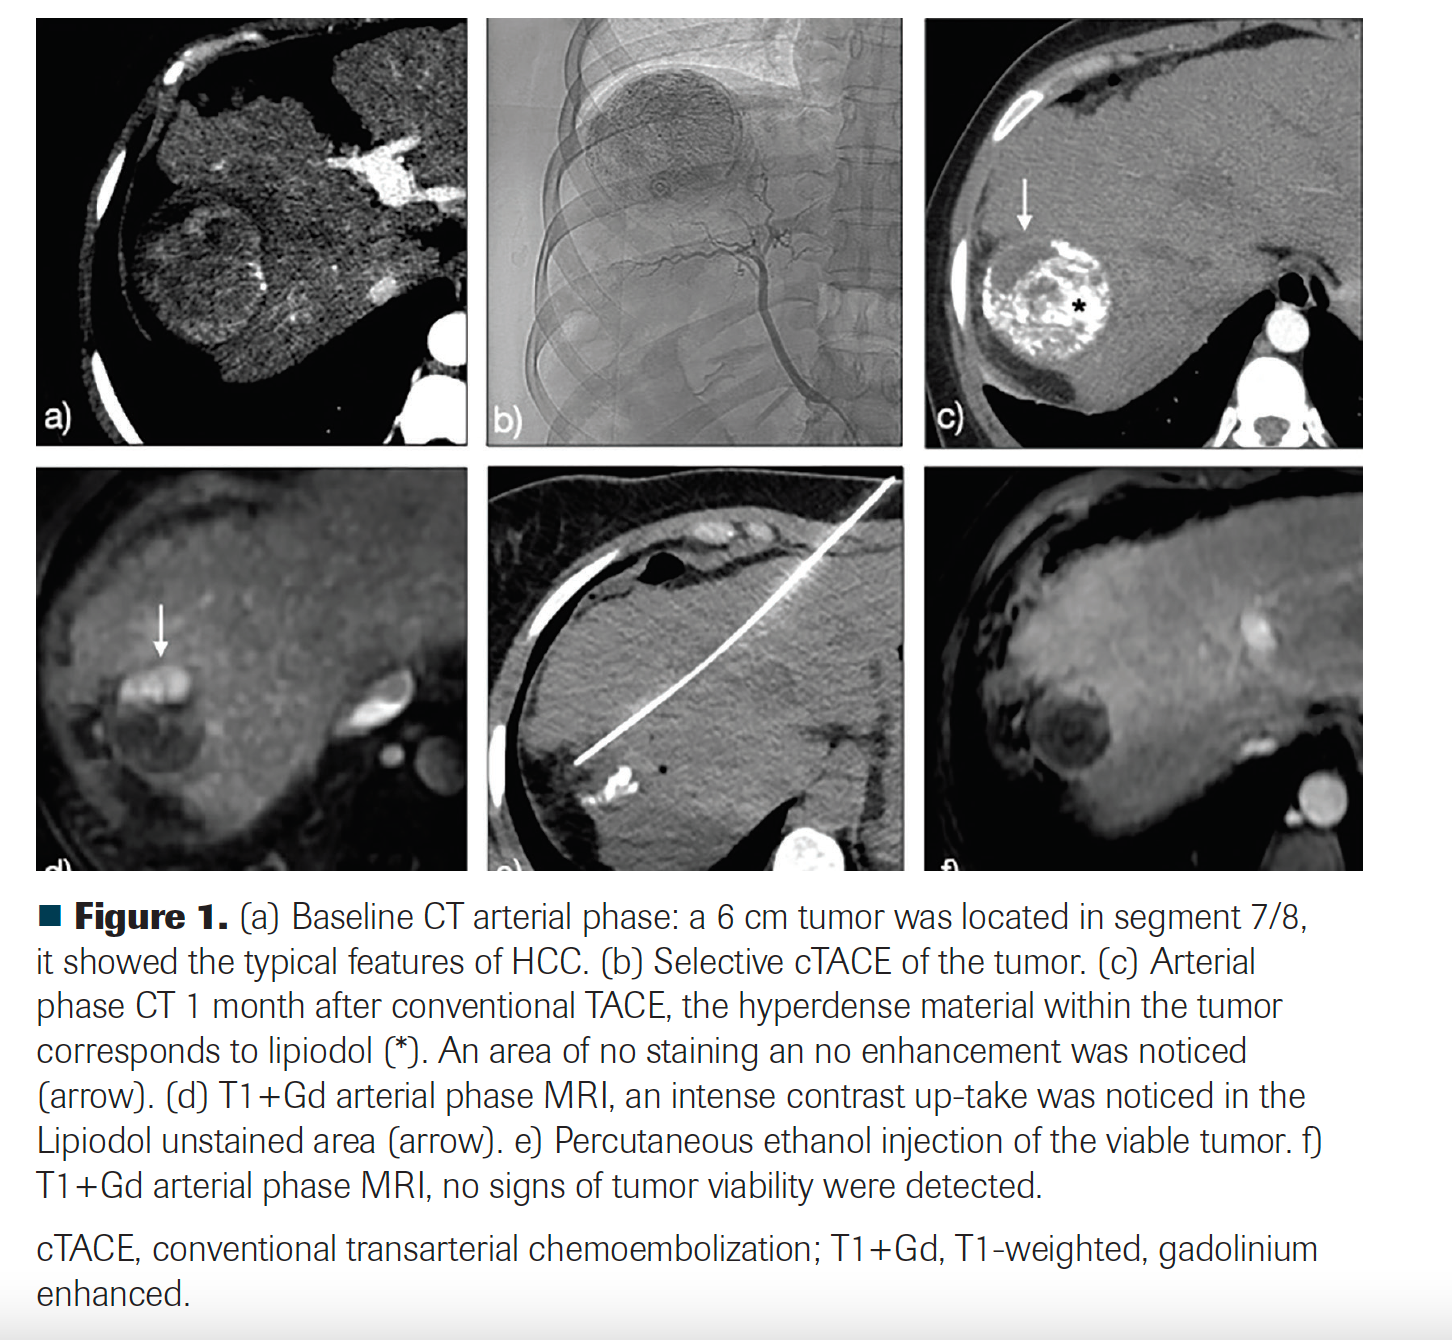

Two weeks after diagnosis, the patient underwent a conventional transarterial chemoembolization (ethiodized oil [Lipiodol] plus doxorubicin, and polyvinyl alcohol [PVA] particles as embolic agent). The first follow-up was done with a multiphase CT 1 month after transarterial chemoembolization. No arterial enhancement was noticed, but there was a 2-cm area of absent ethiodized oil uptake within the tumor. Because of a high suspicion of tumor persistence, MRI was immediately performed, which showed a 1.8-cm viable residual tumor. A bland embolization with PVA particles was performed because of a doxorubicin shortage. Stable disease was documented. Due to residual tumor size and lack of response to transarterial embolization, a percutaneous ablation was performed. Because of the proximity of the tumor to the diaphragm, chemical ablation with ethanol was employed. Four weeks post treatment, an MRI showed a complete response.

FIGURE 1